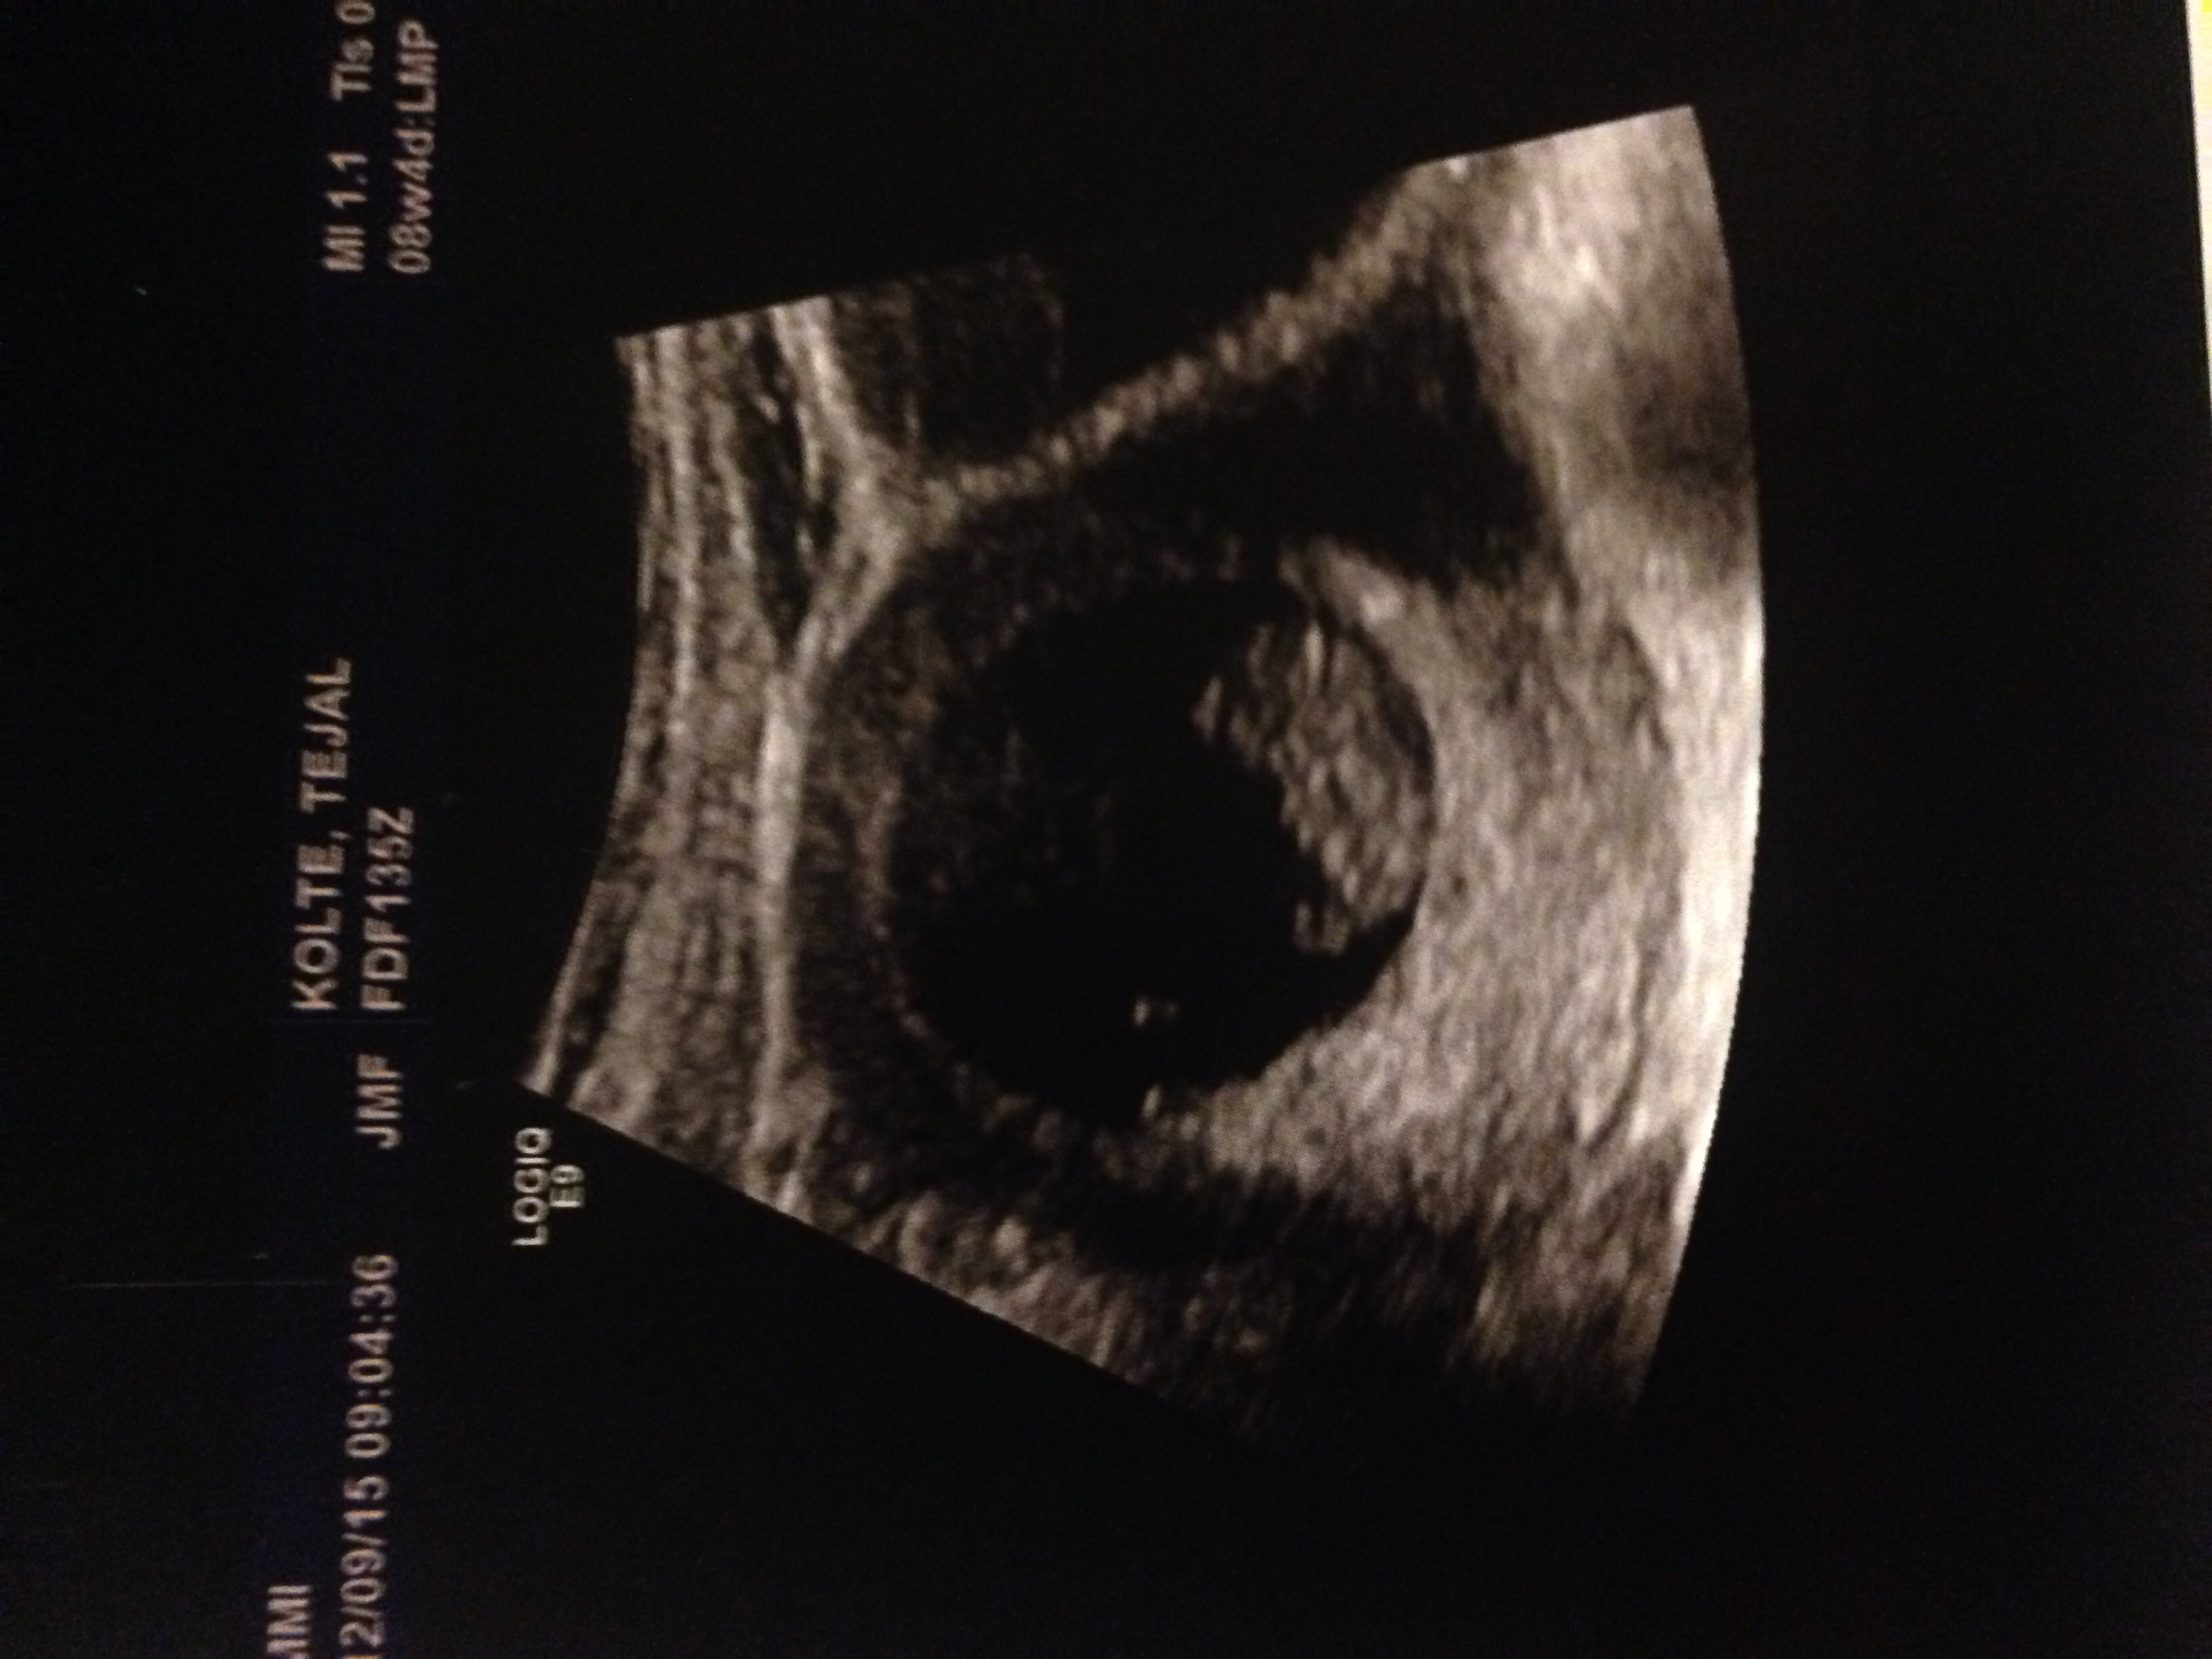

hey beautiful ladies how many of you have had your first ultrasound? How was your experience? I couldnt hold my tears when i saw the tiny being inside me with its heart beating. Such a wonderful thing to experience really:) my husband just couldnt hold smiling and looking away from the baby. Absolutely loved the experience. Here is the pic of the first ultrasound. The baby is 8 weeks 5 days as of today. Please share your experience. Would love to know :)